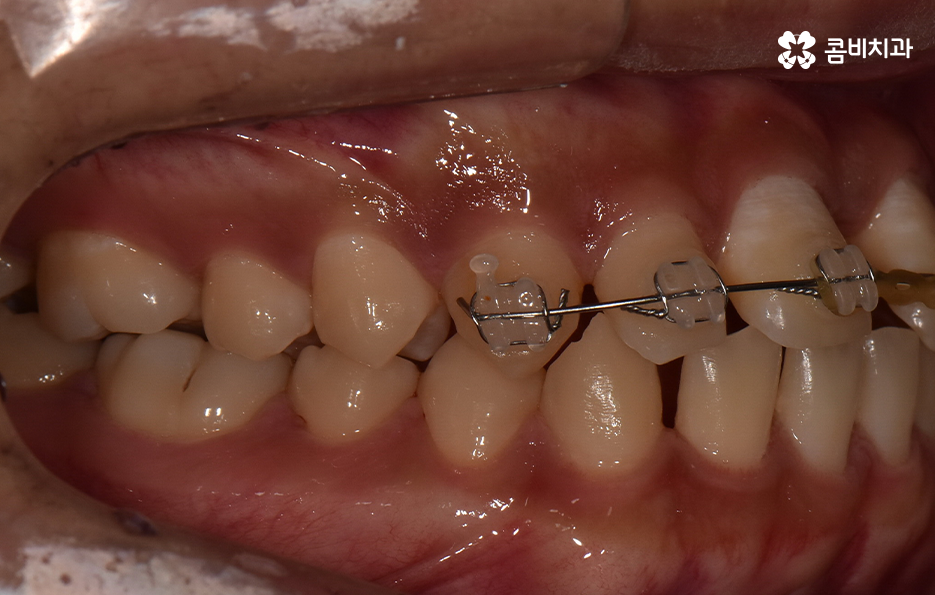

과잉치 중에서는 어떤 치아가 과잉치인지 구분이 어려울 정도로 일반적인 정상 치아의 크기와 비슷한 크기와 형태를 띄는 경우도 있는 반면에 위 사진의 케이스는 첫번째 앞니와 앞니 사이에 유독 작은 왜소치가 있는 형태이기 때문에 치아의 기능적인 문제 보다는 심미적인 개선을 필요했던 케이스로 볼 수 있어요

그나마 다행인 점은 앞니만교정을 하더라도 치아의 교합이나 골격적인 부분, 얼굴형 등에 있어서 큰 지장은 없던 경우였는데요. 물론 아랫니가 다소 벌어져 있기 때문에 전체교정을 하면 더 좋은 결과를 얻을 수 있었겠지만 환자분의 니즈에 있어서 앞니만교정을 빠르게 원했던 사례이기 때문에 앞니 부분의 과잉치 발치 후 앞니만교정을 부분적으로 진행했어요

과잉치로 인해서 치아 배열이 전체적으로 불규칙해지는 경우도 있고 돌출입의 형태로 나타는 경우도 있지만 다행이도 입술라인이나 얼굴형에 있어서 돌출은 크지 않은 상태였다는 점도 앞니만교정을 해도 어느정도 좋은 결과를 낼 수 있던 케이스로 볼 수 있어요

과잉치로 인해 말그대로 치아의 정상 범위 이상으로 치아가 배열되기 때문에 다른 치아의 배열에도 악영향을 주는 경우가 많지만 위 환자분의 케이스의 경우에는 치열 자체는 전체적으로 가지런한 편이라는 점과 특히 턱뼈가 넓은 편이라는 점에서 전체교정을 하지 않았어도 환자분이 원하는 치료의 목표는 달성할 수 있었어요